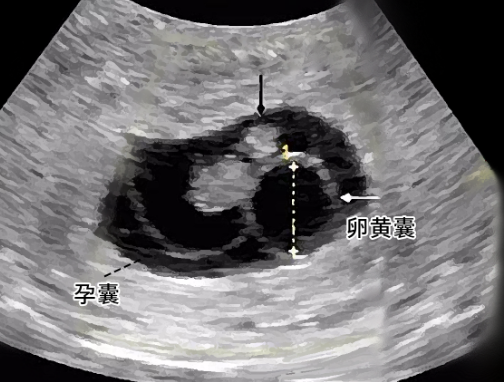

卵黄囊是包裹在孕囊内的早期胚胎组织,先有孕囊然后才有卵黄囊,且随着孕周增大而逐渐增大,一般在怀孕6-7周左右,卵黄囊才会出现,才会促使胚胎进一步发育,如果孕囊中没有出现卵黄囊,这可能表明胚胎的发育出现了问题。在正常情况下,卵黄囊是孕囊内胚胎的早期结构之一,它是孕囊内部的囊状结构,通常在胚胎周围形成。卵黄囊提供了营养和支持,帮助胚胎在早期发育阶段生长。

孕囊内没有卵黄囊可能意味着胚胎发育出现了问题,这可能包括胚胎停止生长或其他异常。这种情况通常需要医生进行进一步的评估和监测,以确定胚胎的健康状况。医生可能会建议进行超声检查、血液检查或其他检查来评估胚胎和孕囊的情况,以确定是否需要采取进一步的治疗措施。

总之,在孕囊直径发育到2.5cm左右时,如果卵黄囊还没有出现那么表明胚胎发育出现了问题,需要进行进一步的评估和监测。相反的,如果在孕囊发育过程中能够清晰看到卵黄囊那么说明胚胎符合初期的发育标准,此时注意产检才能够帮助胚胎正常健康的发育。